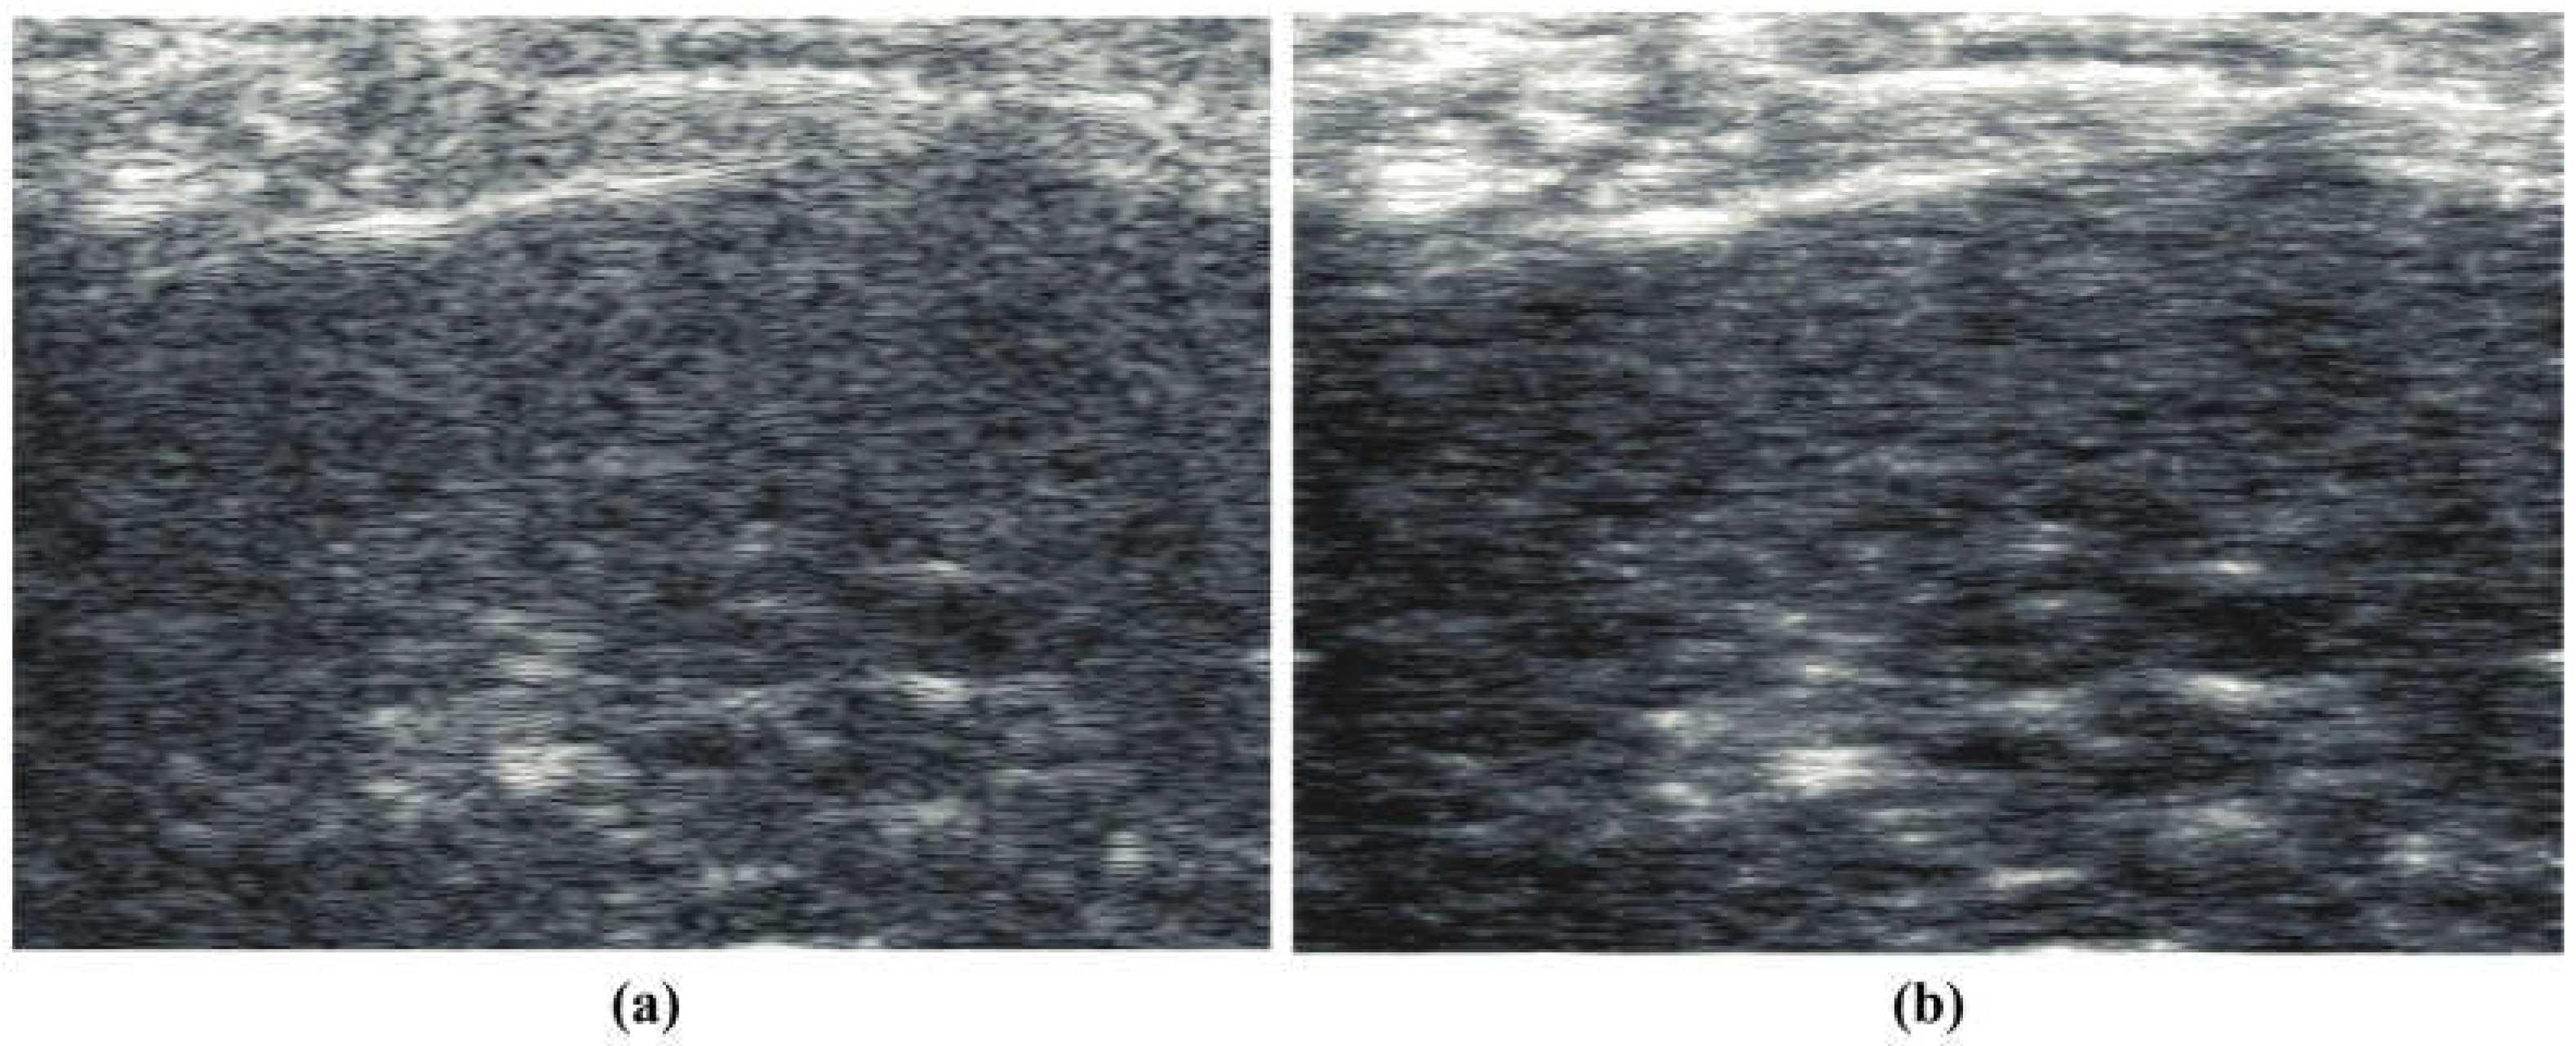

Similarly, a B-scan from a subject on a steatotic diet [] is shown in Figure 2a, demonstrating the classic general hyperechoic pattern as compared to normals. The corresponding “thru-scan” is shown in Figure 2b. Again, a pattern of possible fluid channels (hypoechoic spaces) along with small hyperechoic foci is seen throughout the background scattering amplitude. Compared with the normal liver’s constrained reconstruction (Figure 1b), the steatotic liver in Figure 2b appears more hyperechoic, and the hyperechoic spots are distributed throughout the liver. The speckle pattern within the liver in Figure 2a from the conventional envelope has a mean/standard deviation ratio of 1.97, close to the theoretical Rayleigh speckle ratio of 1.91 expected from ensembles of subresolved scatterers []. In comparison, the constrained power law reconstruction of Figure 2b has a mean/standard deviation ratio of 2.18, indicating a higher value of what Burkhardt termed as the “signal to noise” ratio of speckle patterns []. Similar trends are seen in the processing of human livers at 3 MHz, normal vs. steatotic, but these images are not available at this time for distribution, only by request.

Figure 2.

(a) Conventional B-scan at 15 MHz from a diet-induced steatotic mouse liver, in vivo. (b) constrained reconstruction from power law principles, which we call “thru-scan”, demonstrating a modified background and the emergence of specific hyperechoic points. The images are displayed conventionally using log-compressed 50 dB dynamic range grayscale.